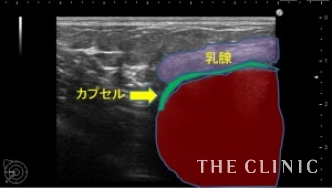

エコー所見です。

右のバッグの周囲のカプセルは肥厚して石灰化が疑われます。

わずかですが、バッグの周囲にシリコンが漏れています。